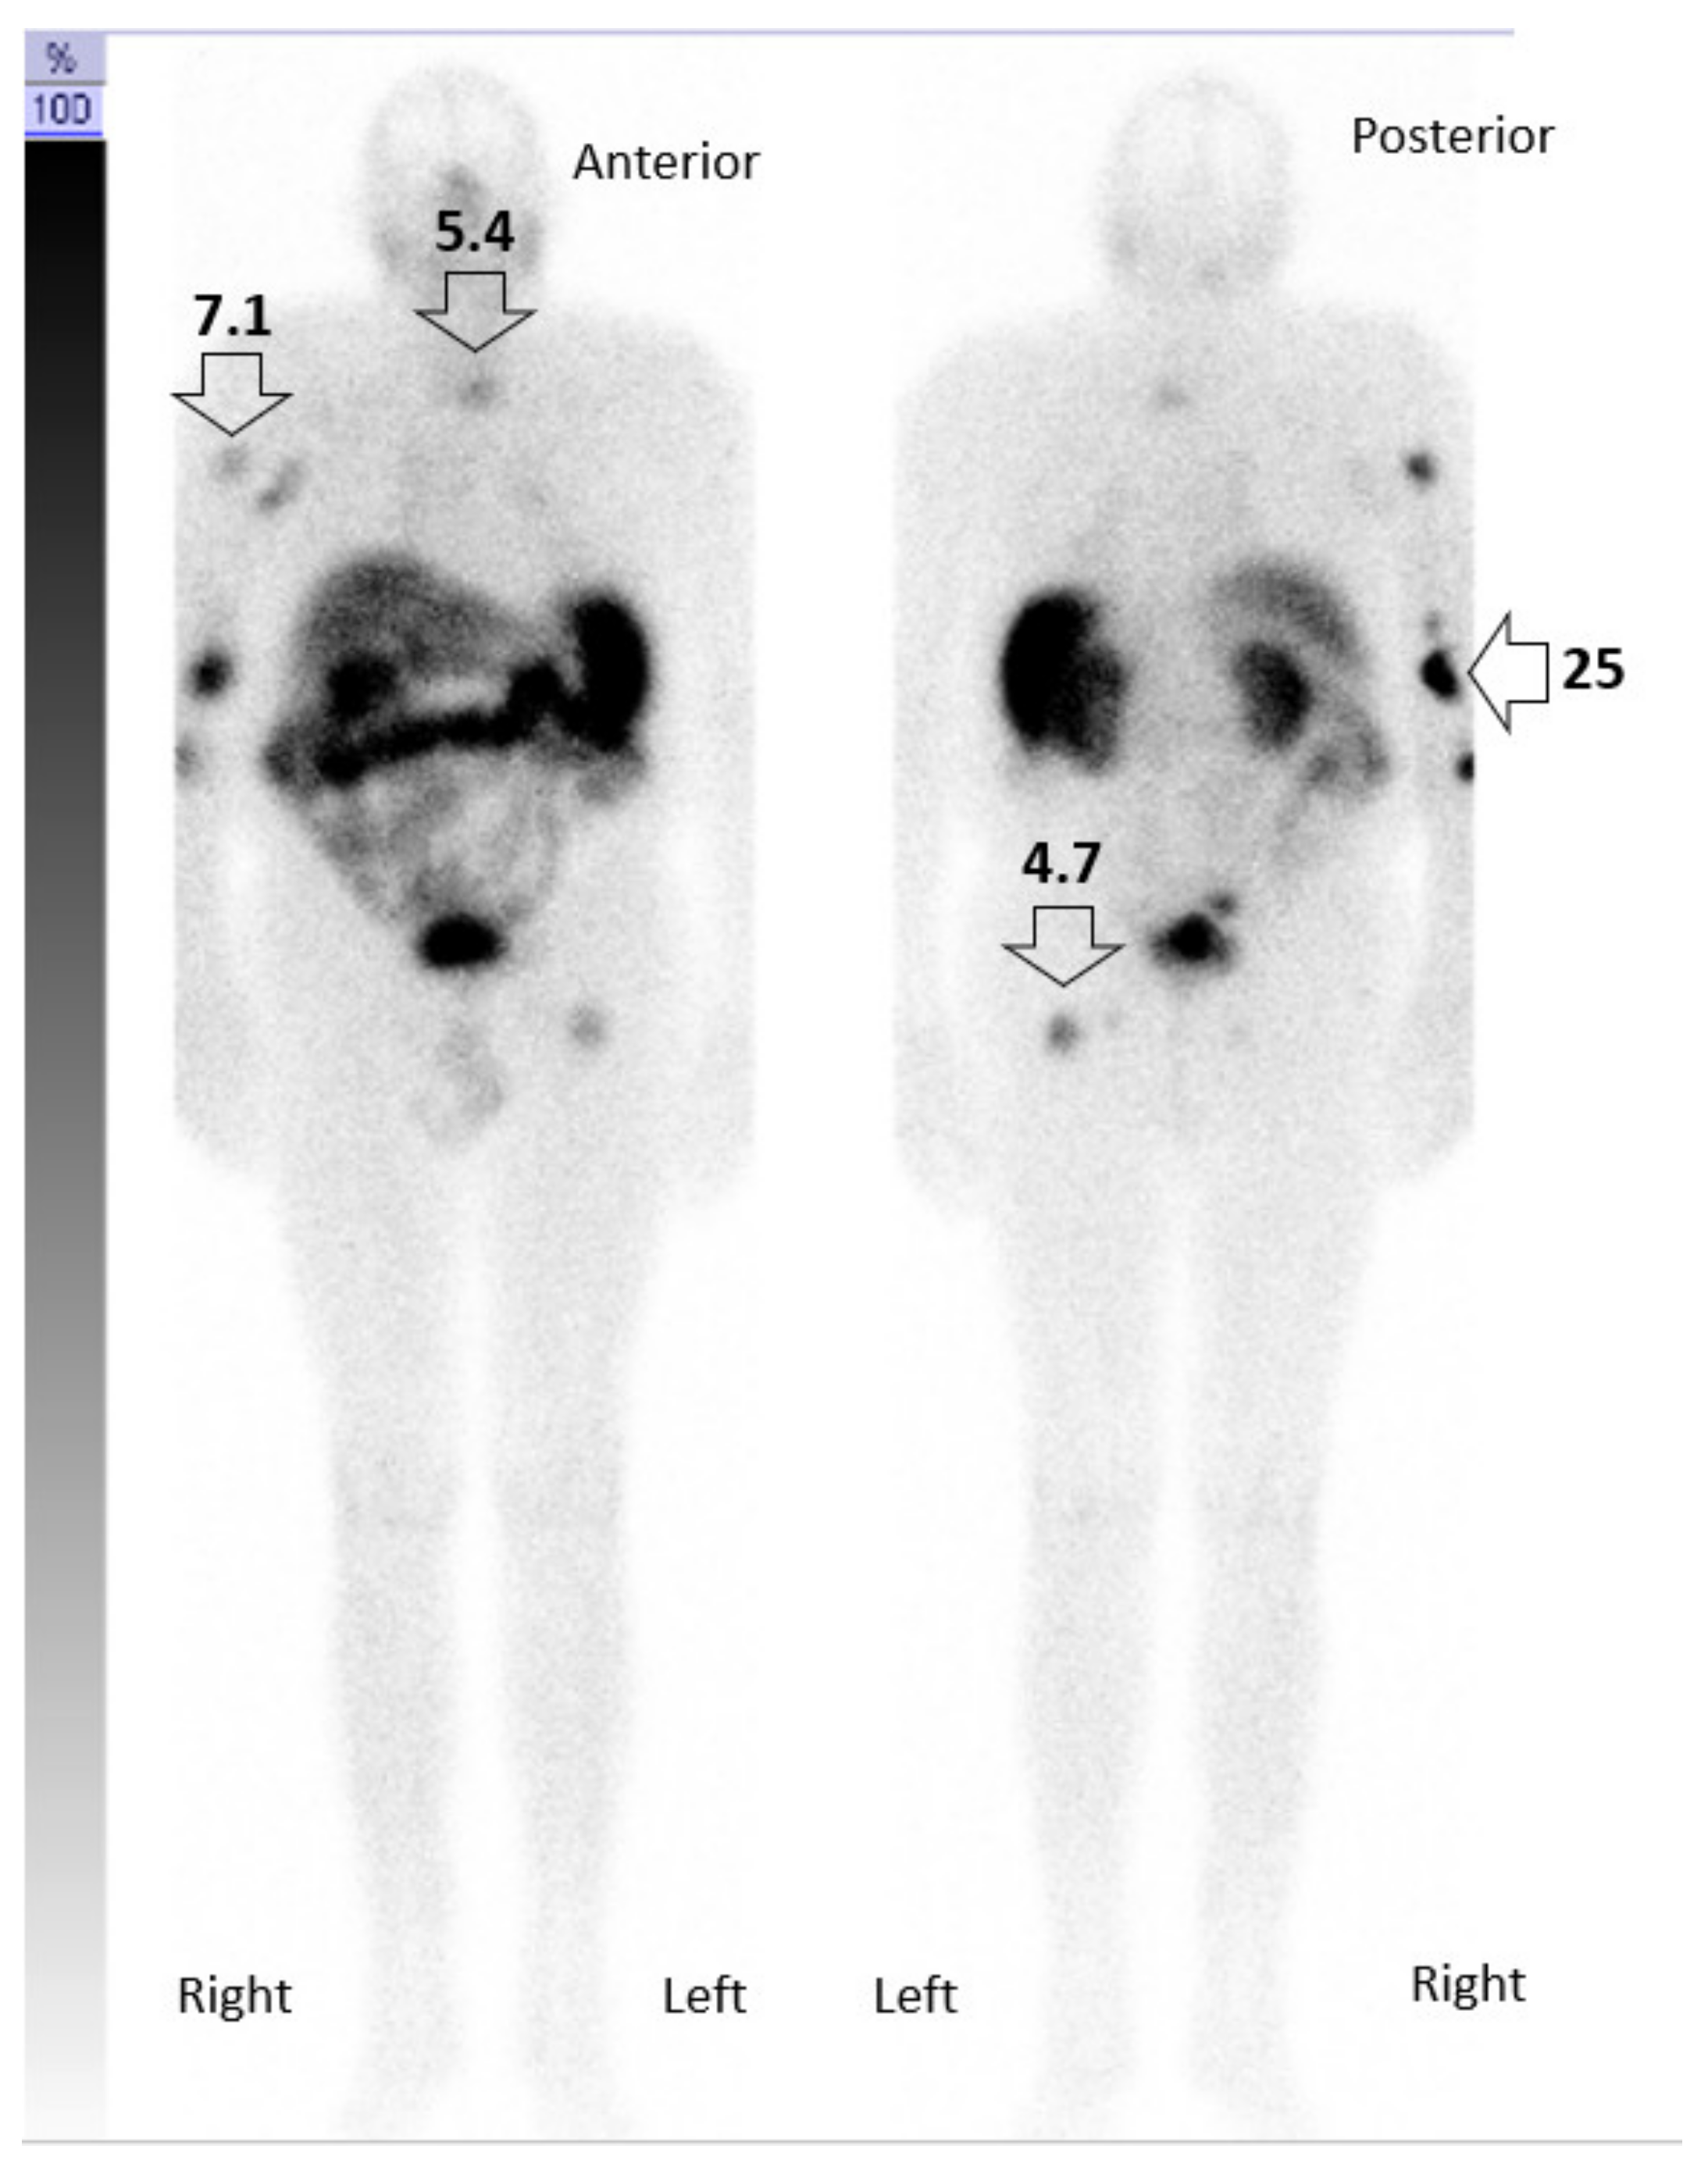

3. Case Description